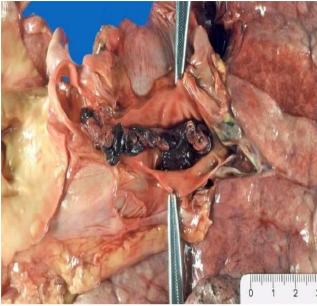

Arteria polmonare con trombo-embolia.